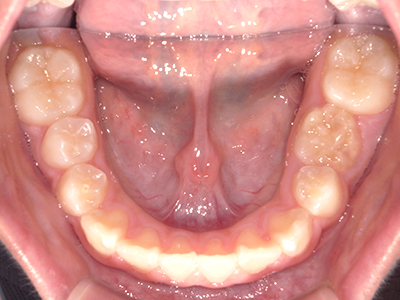

歯並びの相談に来られるお子様は、口呼吸をしているケースが多く、これが歯並びに大きな影響を与えています。

- 口呼吸をしている

↓ - 舌の位置が悪くなる

↓ - 頬の圧力が上の歯列にかかりやすくなる

↓ - 上あごが狭くなる

↓ - 下あごが狭くなる・下あごの位置が悪くなる

↓ - さまざまな不正咬合が生じる

ないき歯科クリニックでは、上あごの成長不足を補い、鼻呼吸を獲得しつつ歯列を整え、将来のお口をより健康な状態にすることをゴールに定める矯正治療をおこなっています。